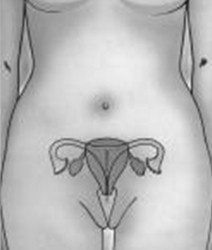

Un dispositivo intrauterino (DIU) es un dispositivo especial que se coloca dentro del cuerpo uterino. Hay más de un tipo de dispositivos. El dispositivo intrauterino se coloca en el útero a través de la vagina y protege del embarazo.

La colocación del Dispositivo intrauterino (DIU) lleva solo 10 a 15 minutos. El Dispositivo intrauterino (DIU) se colocará previa dilatación del cuello del útero, y luego pasando a través del mismo se lo ubica en el útero. Se lo coloca mediante un aplicador especial que lo mantiene cerrado y plano, hasta que llega al fondo del útero. Puede sentir contracciones durante la colocación, pero en general no son intensas.

Previo a la inserción de un Dispositivo intrauterino (DIU), se debe realizar una exploración completa del útero, para determinar el tamaño, comprobar que no existe ninguna infección relevante en el aparato genital y realizar una citología, para descartar cualquier enfermedad del cuello uterino. Además, es en esta primera visita cuando el médico deberá informar a la mujer de los riesgos y de las posibles alternativas de la anticoncepción.

La colocación del Dispositivo intrauterino (DIU) no suele ser dolorosa aunque si algo molesta; la forma del útero, la dilatación del cuello uterino y, cómo no, la relajación de la mujer son datos influyentes.

La inserción no suele durar más de diez minutos y consiste en introducir el Dispositivo intrauterino (DIU) en una vaina de escaso diámetro a través del orificio cervical del útero, y conducirla con delicadeza hasta el interior de la cavidad uterina, en donde el médico descarga el Dispositivo intrauterino (DIU) una vez que considere que se encuentra ubicado en el lugar correcto. Posteriormente, se cortan los hilos a 2 cm del cuello uterino.